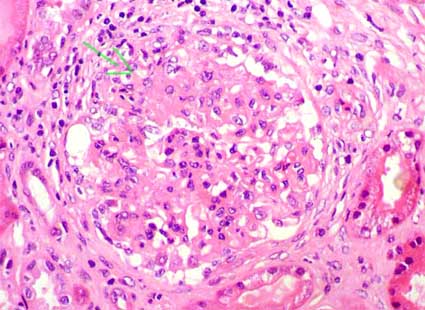

Glomerular changes are highly variable. The commonest alteration is the presence of mesangial and/or capillary immune deposits. Other changes include: increase of the matrix and/or mesangial cellularity, endocapillary proliferation, thickening of capillary walls, glomerular tuft necrosis, extracapillary proliferation (crescents), karyorrhexis, hyaline thrombi (micronodular intracapillary aggregation of immune complexes), and glomerular sclerosis (segmental or global). Some features are suggestive of lupus nephritis: hyaline thrombi and “wire loop” lesions (homogenous and “rigid” thickening of peripheral capillary loops due to subendothelial immune deposits), nevertheless, the only alteration considered by many authors as pathognomonic of lupus nephritis are the hematoxylin bodies: they are rounded, smudgy, lilac-staining structures, seen as cells with degenerated aspect; probably they represent degenerated nuclei and correspond to LE cells described in the blood of patients with SLE (figure 4); it is very unusual to find them at the present, reason why its utility is very limited (sensitivity near 2%). The variability in the presence, combination and extension of these lesions permit to classify lupus nephritis based on histologic aspects (Figures 1, 2, 3, 4, 5, 6, 7, 8, 9, 10 and 11).

Figure 1. Glomerular tuft with proliferation of mesangial cells, segments with endocapillary proliferation, and a small circumscribed crescent (arrow). In lupus nephritis active proliferation and glomerular changes are frequently segmental; nevertheless, to determine if it is class III (focal) or IV (diffuse) it is necessary to quantify the percentage of glomeruli with lesions (H&E, X400).